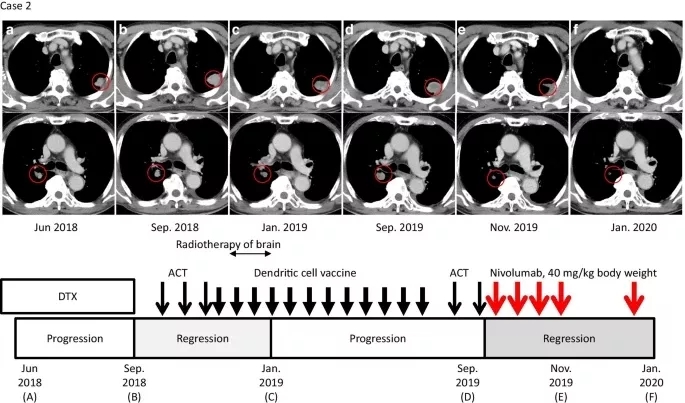

患者于2018年10月至作者医院接受ACT,随后以2~3周的间隔进行3次αβT淋巴细胞的ACT,直到2018年12月。2018年12月26日到2019年6月28日,患者共接受了12次(间隔2~3周)应用MUC1、MAGE3和survivin的树突状细胞(DCs)脉冲治疗(图2),MUC1、MAGE3和survivin均作为肿瘤抗原在其肿瘤细胞上表达。在ACT和脉冲DC治疗期间,2018年11月发生脑转移,接受了脑转移立体定向放疗。常规CT显示,多个肺和淋巴结的转移病灶缩小,根据2019年1月实体瘤反应评价标准(RECIST)1.1版评估为部分缓解(图2c)。此外,2019年4月脑转移病灶也有所减少。

2019年9月,随访CT显示肺和肺门淋巴结转移灶再生,患者开始每月接受一次ACT治疗(图2d)。免疫组化染色显示肿瘤中PD-L1表达水平为1%,MSI阴性(数据未显示)。ACT后,患者接受纳武利尤单抗治疗(剂量为0.6 mg/kg体重,4次,每隔2周一次)作为诱导治疗的一部分。

2019年11月27日(纳武利尤单抗启动后8周)的随访CT扫描显示部分缓解,肺部病灶及和肺门部淋巴结肿块减少60%(图2e)。患者继续接受每隔3周一次、剂量为40 mg/kg体重的纳武利尤单抗治疗作为维持治疗。在患者2019年的临床病程中,放射学证据显示病变持续改善,由于患者临床状态良好且存活,因此继续使用纳武利尤单抗维持治疗(图2f)。在联合治疗期间没有不良事件的证据。

图2. 病例2临床病程

与治疗和疾病状态时间线相对应的轴位CT图像。红色圆圈表示肺和肺门转移性病变。a. (上)多西他赛(DTX)给药期间的状态。b. 过继细胞疗法(ACT)治疗前肺转移进展情况。c. ACT和树突状细胞(DC)疫苗治疗后肺转移的消退。d. 服用纳武利尤单抗前肺和肺门淋巴结转移的进展。e. 免疫检查点抑制剂(ICI)与ACT联合治疗8周后肺转移消退。在使用ICI维持治疗期间,缓解是持续的(f)。窄的黑色箭头、粗体黑色箭头和红色箭头分别表示ACT、DC疫苗和纳武利尤单抗给药(下)。